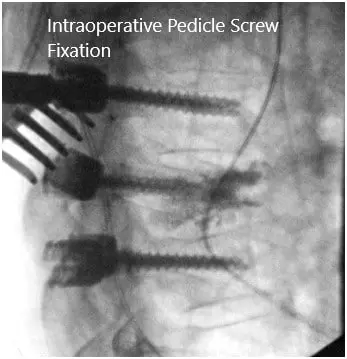

Intraoperative fluoroscopic images.

At this point, given the location of the fracture and the severity, we then moved to finish our instrumented fusion from T5 to T7. The pedicles of T6 were cannulated by using the high-speed drill to create a starting point and then we used the pedicle gearshift under fluoroscopy to enter the pedicles.

Using anatomic trajectories, we then tapped these pedicles to start and inserted 4.5 x 30 mm pedicle screws on both sides. We confirmed our trajectories using fluoroscopy and triggered EMG. We did the same thing for both the T5 and T7 pedicles probing them using Lenke gearshifts and under fluoroscopy after creating our pilot hole with normal anatomical starting points with the high-speed drill. We inserted 5.5 x 40 mm screws under direct fluoroscopy at the T5 and T7 levels and then applied 5.5 x 65 mm rods, which were secured with caps screws and locked into position.

All six screws were stimulated using trigger EMGs and found to be in a safe position. We then obtained both the final AP and lateral x-rays to ensure the proper positioning of the screws. The wound was washed out copiously with bacitracin irrigation and then the high-speed drill was used to decorticate the bone and the bone chips obtained were then gathered, morselized, and used for autograft.